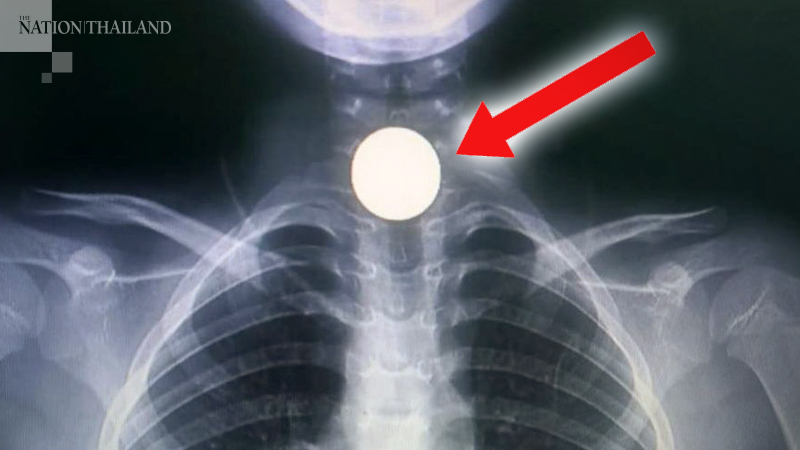

When the child started vomiting, foaming at the mouth and was unable to speak, his parents took him to a hospital nearby, where doctors said the coin was stuck deep in his throat.

The child was then transferred to Sichon Hospital and the coin removed via a surgical procedure.